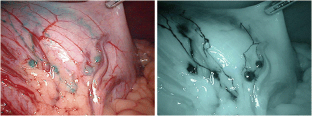

Prospective multicenter trials have shown the feasibility of sentinel node (SN) navigation surgery using a dual tracer of dye and radioisotope for early gastric cancer. However, comparable trials using the indocyanine green (ICG) and the infrared ray laparoscopic system (IRLS) have not been reported. On the basis of our cohort studies, we assumed that the ICG imaging with the IRLS is as effective as the dual tracer in detecting SNs. Therefore, we conducted a prospective multicenter trial to assess the effectiveness and generalizability of the infrared ICG technique in patients with early gastric cancer.

Patients with previously untreated cT1 gastric adenocarcinomas less than 4 cm in gross diameter were eligible for inclusion in this study. SN mapping was performed by using ICG combined with IRLS technique. Following biopsy of the identified SNs, D2 or modified D2 laparoscopic gastrectomy was performed according to the current Japanese Gastric Cancer Association guidelines.

Fig. 1

Fig. 2